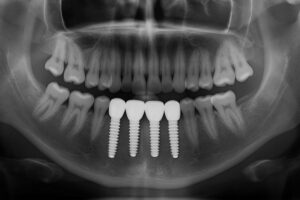

Your first visit includes a clinical exam, digital x-rays or CT scans, and intraoral scans. These tools let the team plan precise implant placement and create surgical guides.

Implant surgery places the titanium post in the jaw. Sedation options range from local anesthesia to IV sedation for comfort. Most patients feel pressure but minimal pain during the procedure.

Osseointegration—the implant fusing to bone—takes several months. After healing, a custom crown, bridge, or denture is attached to the implant.